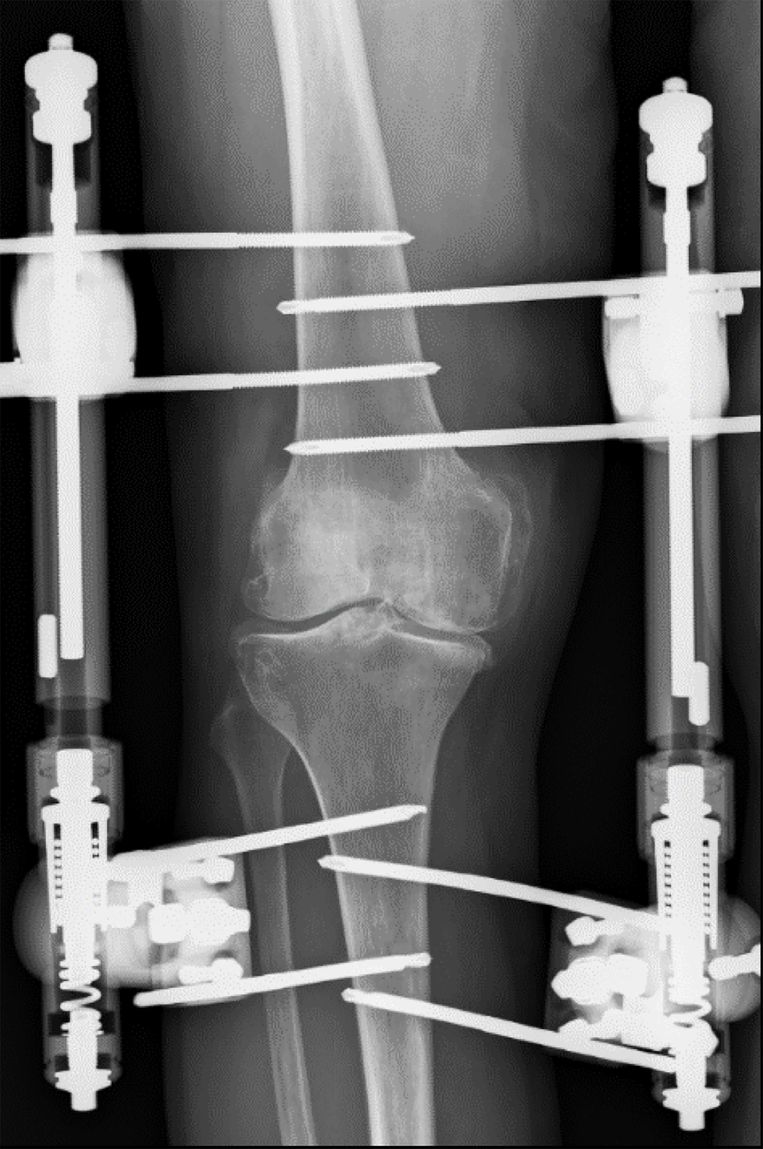

Röntgenfoto Knie Met Vocht . FIGUUR (a) Röntgenfoto van de linker knie van patiënt met dorsomediaal... Download Scientific Depomedrol) is aangewezen bij een acute achteruitgang met vocht in de knie (posttraumatisch, overbelaste of ontstoken knie) Dat kan met ijsblokjes in een plastic zak of een 'ice-pack'

Source: ucgmplsguq.pages.dev FIGUUR (a) Röntgenfoto van de linker knie van patiënt met dorsomediaal... Download Scientific , U kunt uw knie direct na de val of verkeerde beweging koelen Een conventionele röntgenfoto geeft een indruk over de anatomie en positie van de patella

Source: zealisejly.pages.dev XKnie , Op deze röntgenfoto zijn de botstructuren zichtbaar van het dijbeen, het scheenbeen, het kuitbeen en de knieschijf. Kan MRI met vocht in knie? Of heb je knieklachten als gevolg van een (sport)ongeval of trauma? Een MRI scan van de knie is een non-invasieve manier om inzicht te krijgen in te krijgen over de oorzaak van je klachten